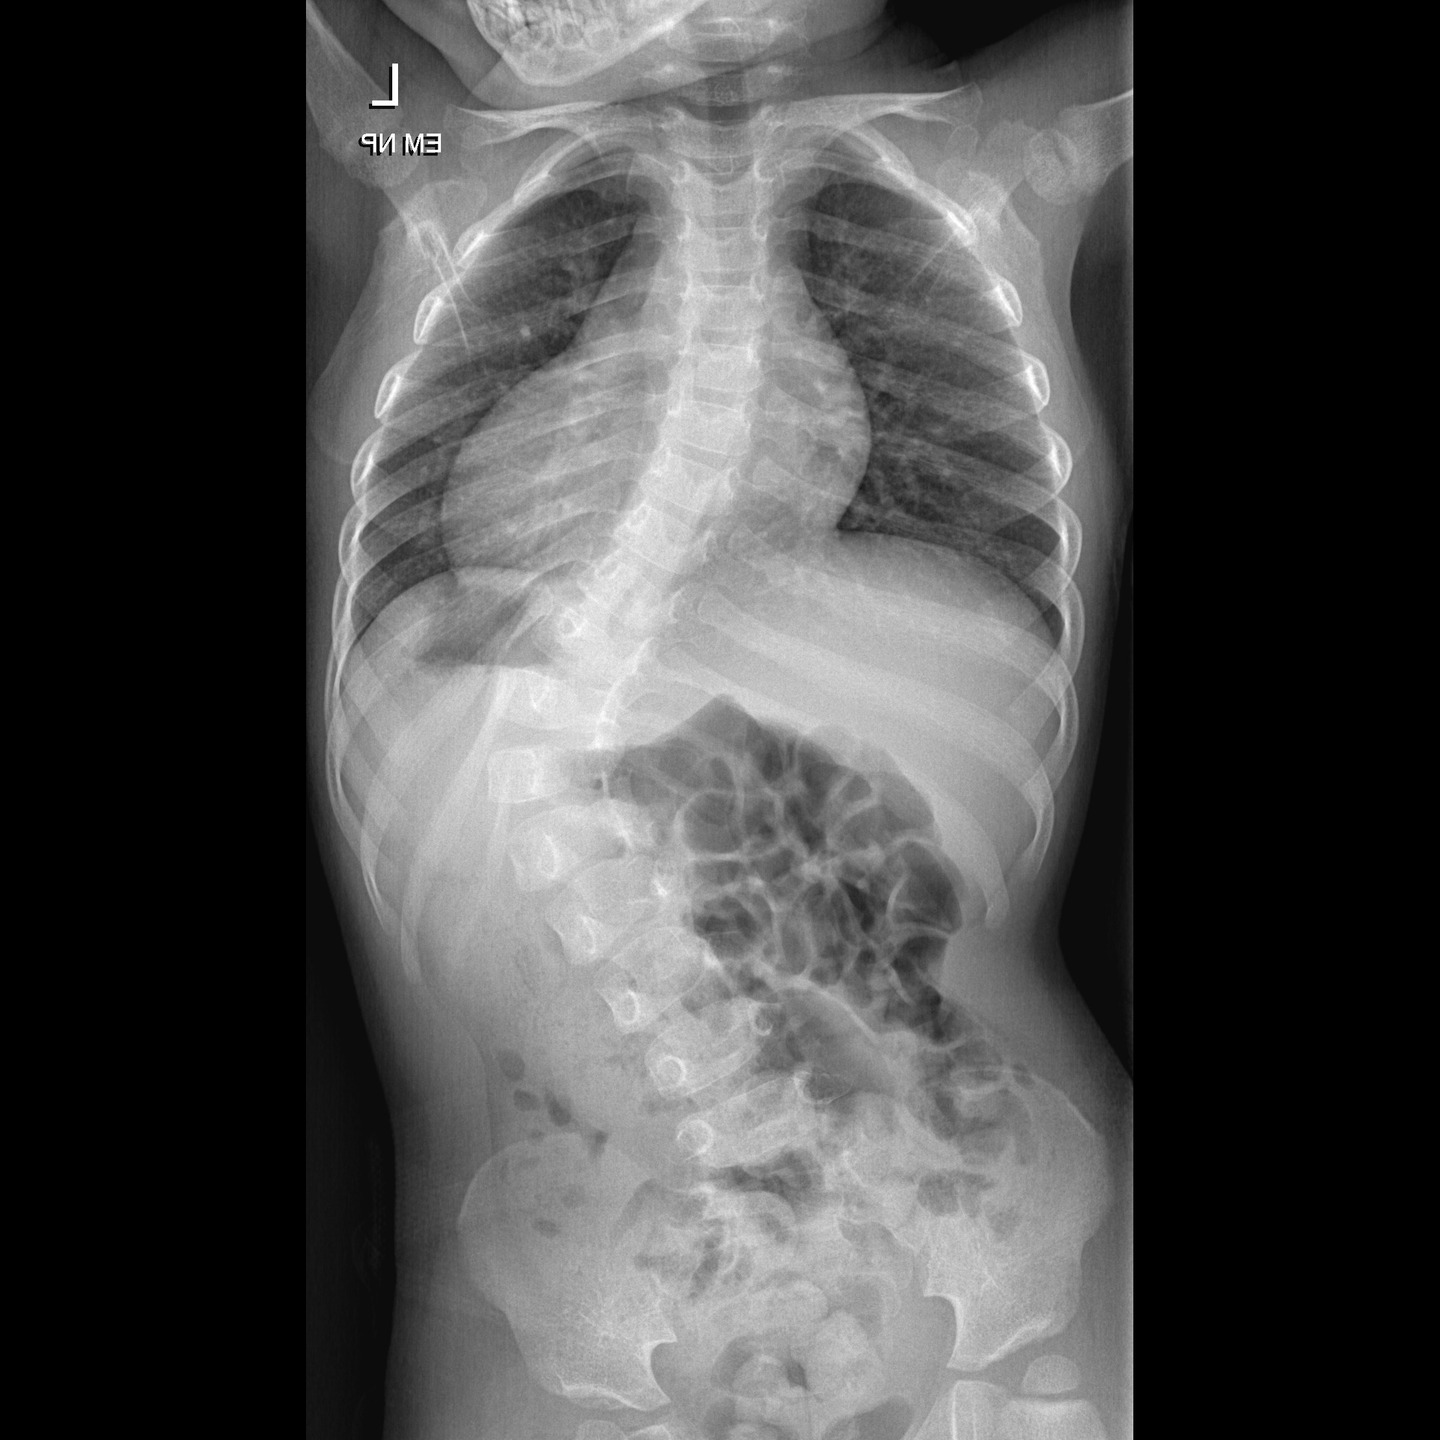

Lekári oddelenia pediatrickej ortopédie a spondylochirurgie žilinskej nemocnice zrealizovali úspešný zákrok u 2-ročného dieťaťa s extrémne ťažkou idiopatickou infantilnou skoliózou. Náročnú diagnózu, ktorá vznikla po narodení a je mimoriadne vzácna, nebolo možné vyriešiť konzervatívnou liečbou. Žilinskí odborníci vykonali operáciu ako prví na Slovensku.

Idiopatické skoliózy sú najčastejším druhom skolióz spomedzi detských deformít chrbtice a ich vznik je typický pre predpubertálny vek. Liečba je vo väčšine prípadov konzervatívna, no ťažké prípady je potrebné operovať, zvyčajne po ukončení rastu dieťaťa. „Výskyt diagnózy v tak nízkom veku, aký mala operovaná pacientka, je mimoriadne vzácny, pričom skolióza postihla celú chrbticu. Takýto prípad sa na Slovensku ešte neoperoval a bola to pre nás veľká výzva,“ uviedol primár Oddelenia pediatrickej ortopédie a spondylochirurgie FNsP Žilina Juraj Popluhár s tým, že chrbtica si u malého dieťaťa vyžadovala aplikáciu dlhého, jemného fixátora, ktorý s ním musí rásť. „Chcem vyjadriť veľké uznanie a vďaku celému tímu oddelenia za ich profesionálnu prácu a mimoriadne nasadenie. To, čo naši odborníci dokázali aj počas tejto operácie je dôkazom ich neoceniteľných zručností na najvyššej úrovni. Žilinské pracovisko je pod vedením Juraja Popluhára lídrom v oblasti pediatrickej spondylochirurgie na Slovensku. Každý krok, ktorý podniká, posúva hranice medicíny a prináša pacientom v ťažkých životných situáciách príležitosť na lepšiu budúcnosť,“ doplnil riaditeľ FNsP Žilina Juraj Kacian.